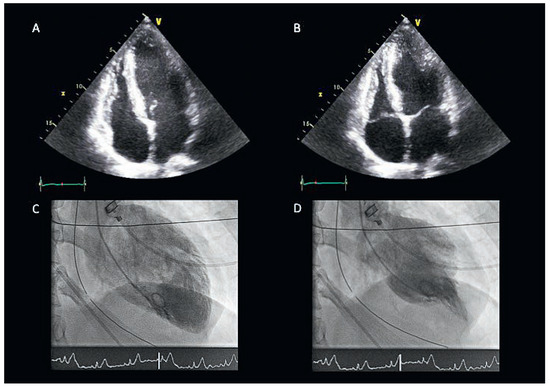

Gunshot Reversed the Tako-Tsubo